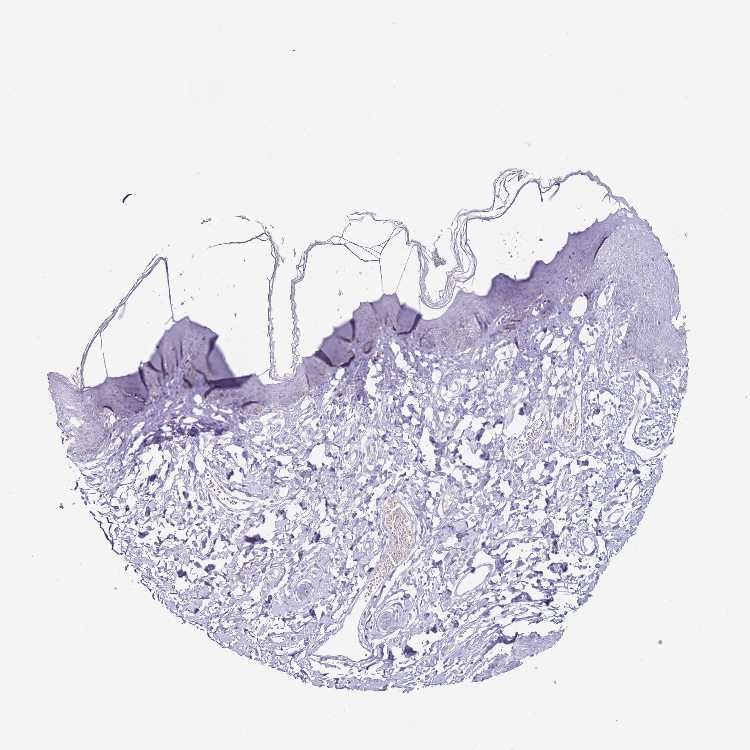

SKIN 1 - Antibody stainingi

Antibody staining in the annotated cell types in the current human tissue is reported as not detected, low, medium, or high, based on conventional immunohistochemistry profiling in selected tissues. This score is based on the combination of the staining intensity and fraction of stained cells.

Each image is clickable and will lead to virtual microscopy that enables deeper exploration of all samples and also displays staining intensity scores, fraction scores and subcellular localization as well as patient and tissue information for each sample.

Antibody HPA045728

Langerhans Not detected

Fibroblasts Not detected

Keratinocytes Not detected

Melanocytes Not detected